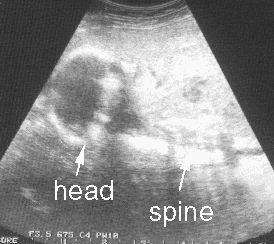

Ultrasound showing Benjamin's head (1)